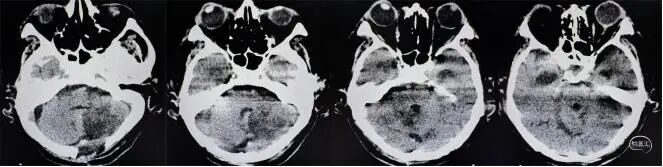

在整个治疗期间,李晓东团队对患者的管理体现了极致的精细与前瞻性。面对术后严重的脑水肿以及梗阻性脑积水,在适时拔除脑室外引流管后,巧妙利用预留的Ommaya囊持续引流脑脊液解决脑积水问题,并定期进行化验,成功避免了颅内感染的发生。目前,患者已能配合完成伸舌、抬腿等指令,并且能够在家属协助下开始下床活动,在整个漫长治疗过程中,未出现下肢深静脉血栓等并发症,也为康复创造了良好条件。

为进一步解决目前患者交通性脑积水问题,为患者后期的神经功能恢复扫清障碍,李晓东主任团队已为患者制定了下一阶段的“脑室-腹腔分流术”计划,并且可以直接通过Ommaya囊连接腹腔端引流管,避免再次穿刺脑组织造成二次伤害。

现患者头部CT▲